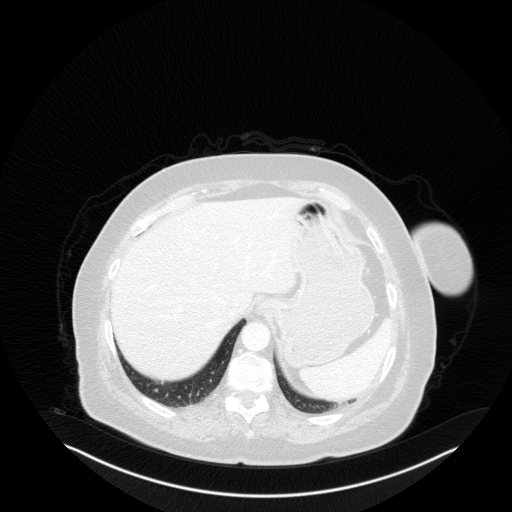

Original VENOUS CT scan

Full window (WL 1023.5, WW 4095 β†’ Low βˆ’1024, High +3071)

Lung window (WL -600, WW 1500 β†’ Low βˆ’1350, High +150)